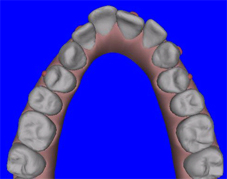

| תמונת שיניים עליונות לפני הטפול | מודל וירטואלי של השיניים העליונות לפני הטפול | |